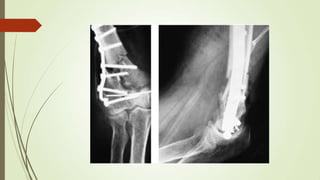

TREATED MONTEGGIA FRACTURE

Ulnar Fracture

Txt Displaced type B and C

 ORIF

 K wire can be used

 unicondylar fracture without comminution can then be

fixed with screws; if the fragment is large, a contoured

plate is added to prevent re-displacement.

 Plates with locking screws